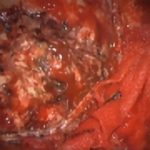

術中写真

摘出 中